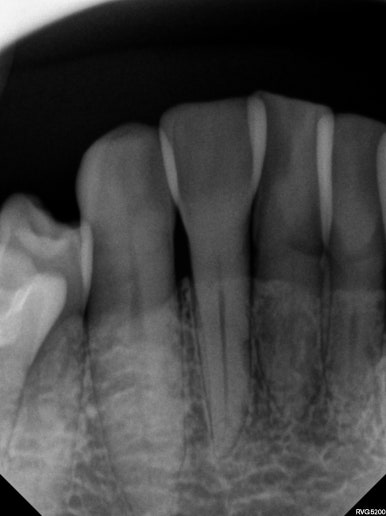

마지막으로 파노라마 엑스레이를 찍고 마무리하였습니다.

보시다시피 모든 치아가 뿌리가 나란하게끔 교정이 마무리 된 것은 아닙니다만, 생리적으로 적절한 교합을 형성하였고 가장 눈에띄는 앞니는 배열을 가지런히 맞추어 내었습니다.

치과용 파노라마 엑스레이를 보았을 때, 특별히 잇몸이 안좋아진 치아도 보이지 않았으며 향상된 치아배열로 인해 구강위생관리 또한 향상되어 있다는 생각이 절로 들었습니다.